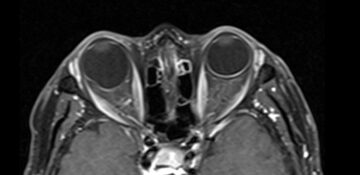

Cortes axiales de resonancia magnética de órbitas en el cual se aprecia aumento del tamaño del globo ocular derecho a expensas de su eje anteroposterior, acompañado de adelgazamiento de su pared posterior lo cual corresponde a estafiloma.

Hallazgos por imagen: Aumento del tamaño del globo ocular y adelgazamiento de sus paredes posteriores.